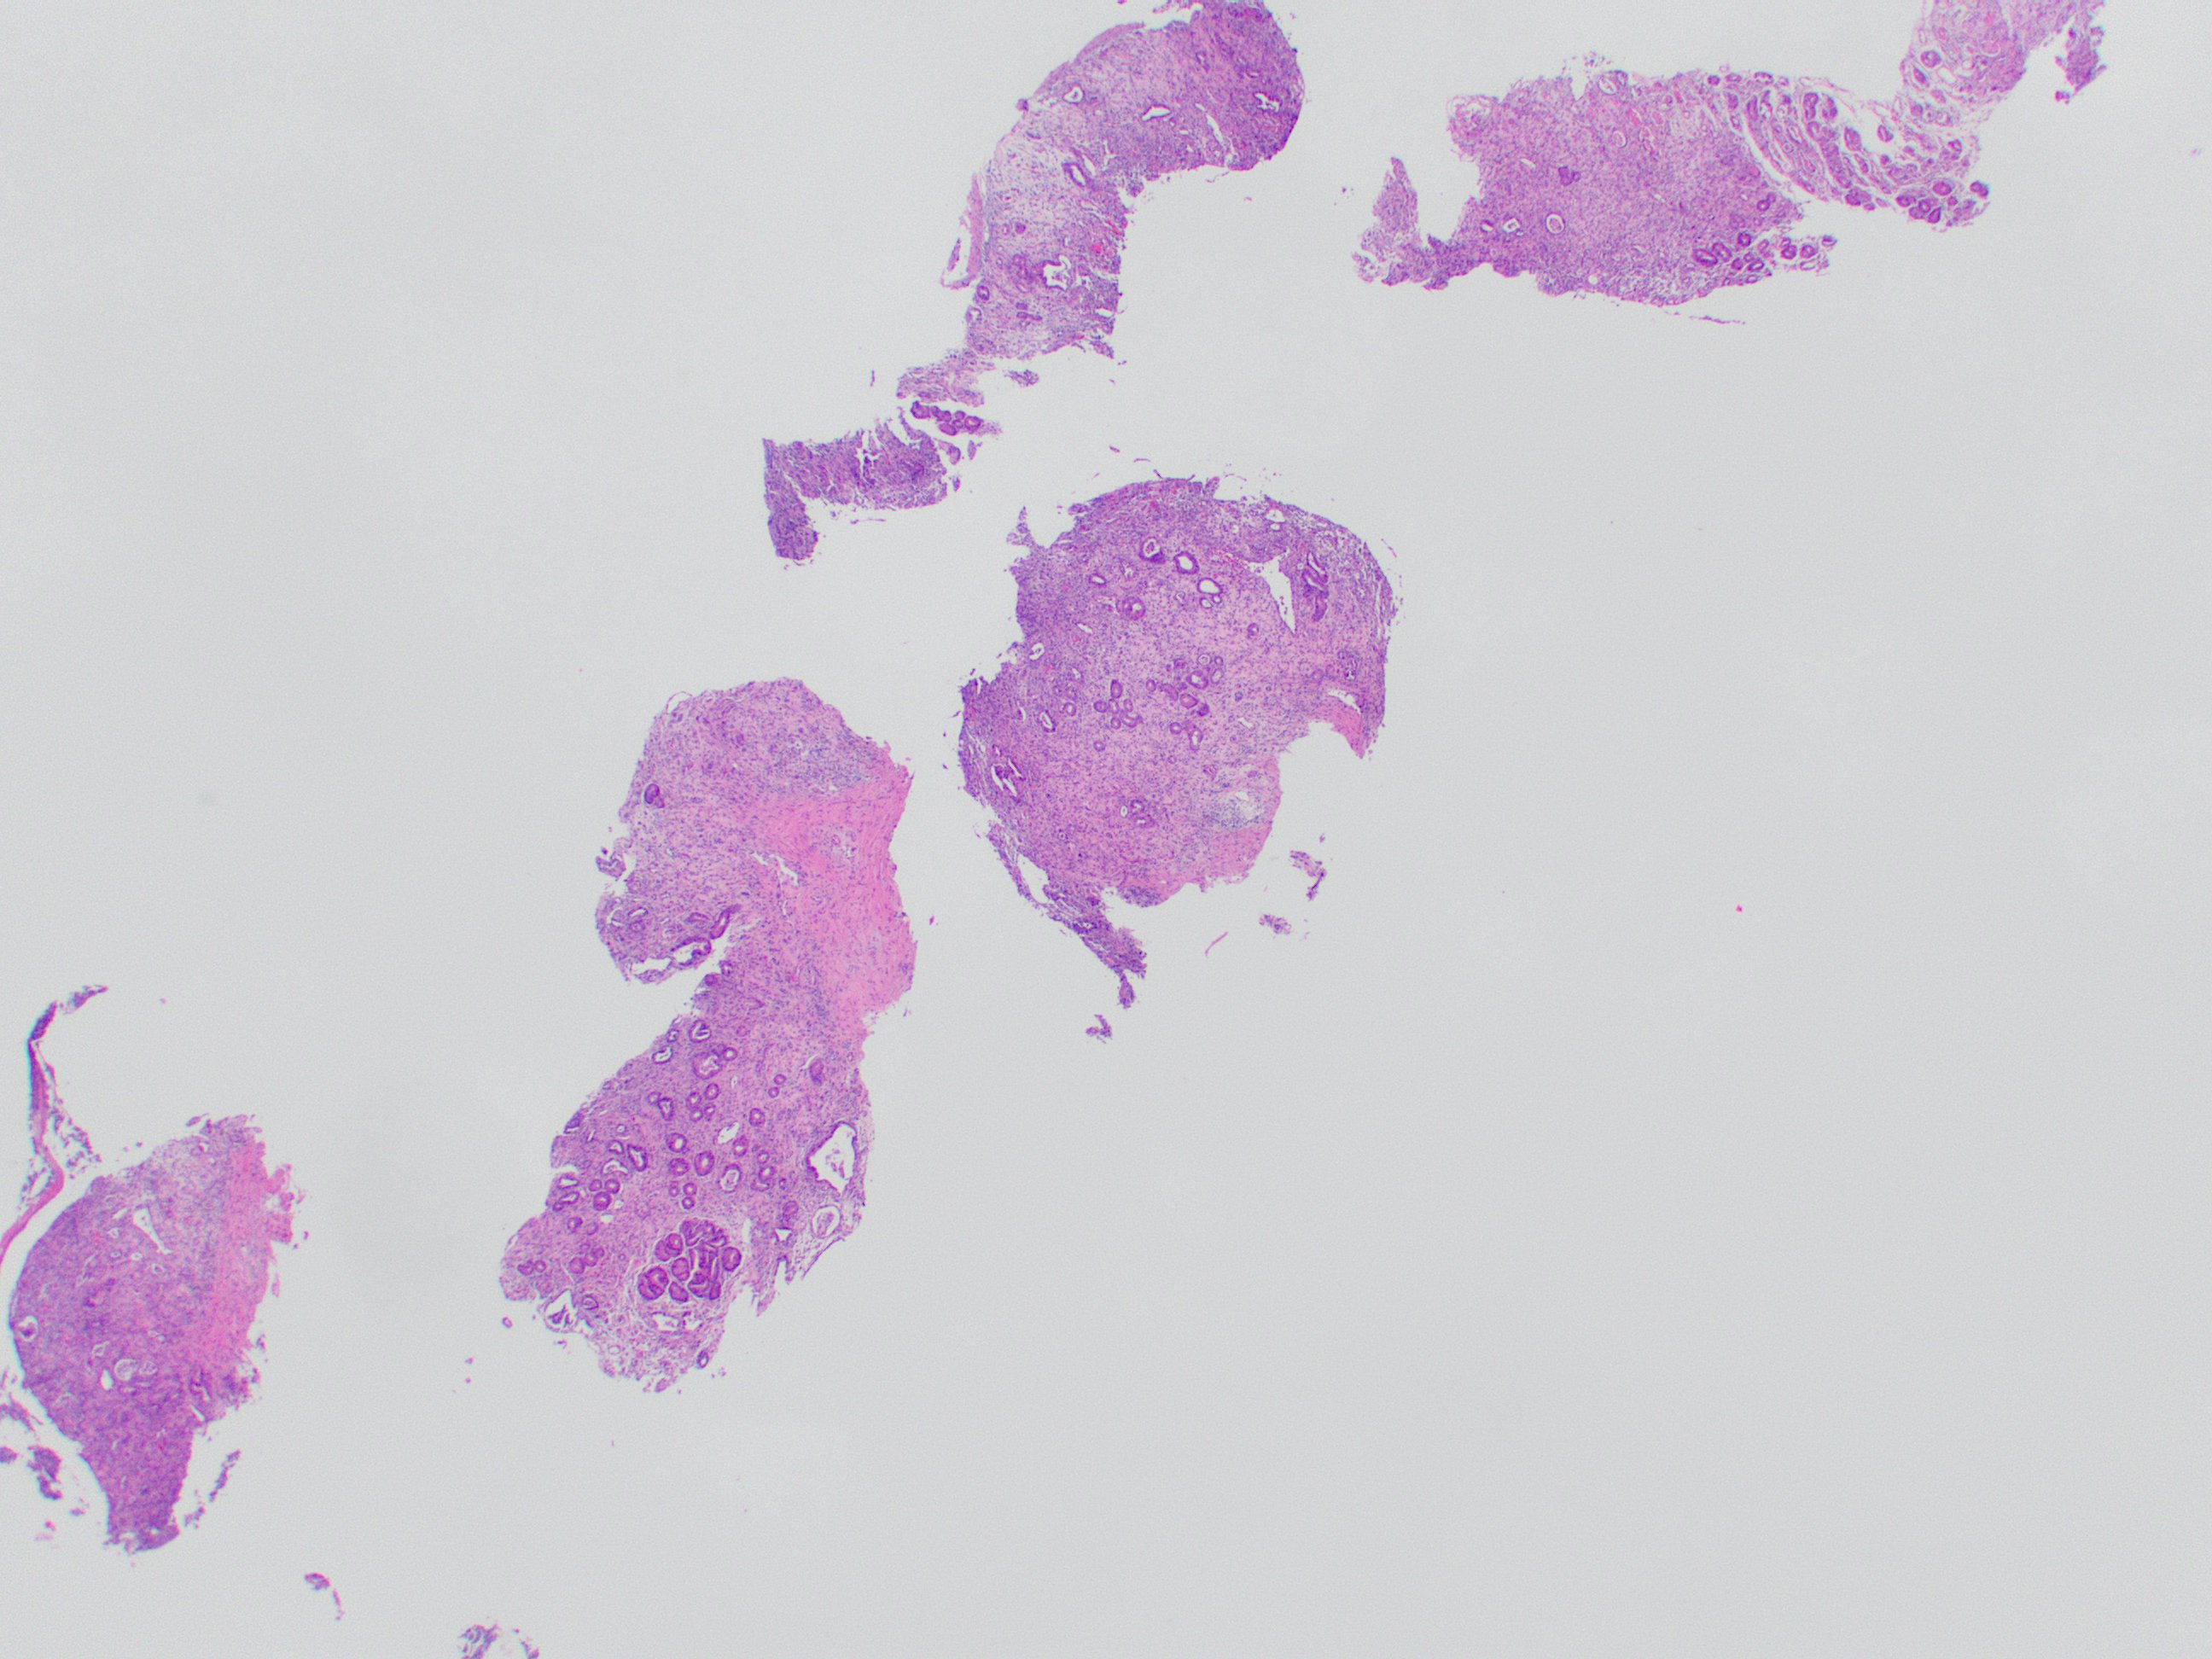

That covers the basics! Here is a direct side-by-side before and after editing in GIMP:

That covers the basics! Here is a direct side-by-side before and after editing in GIMP: